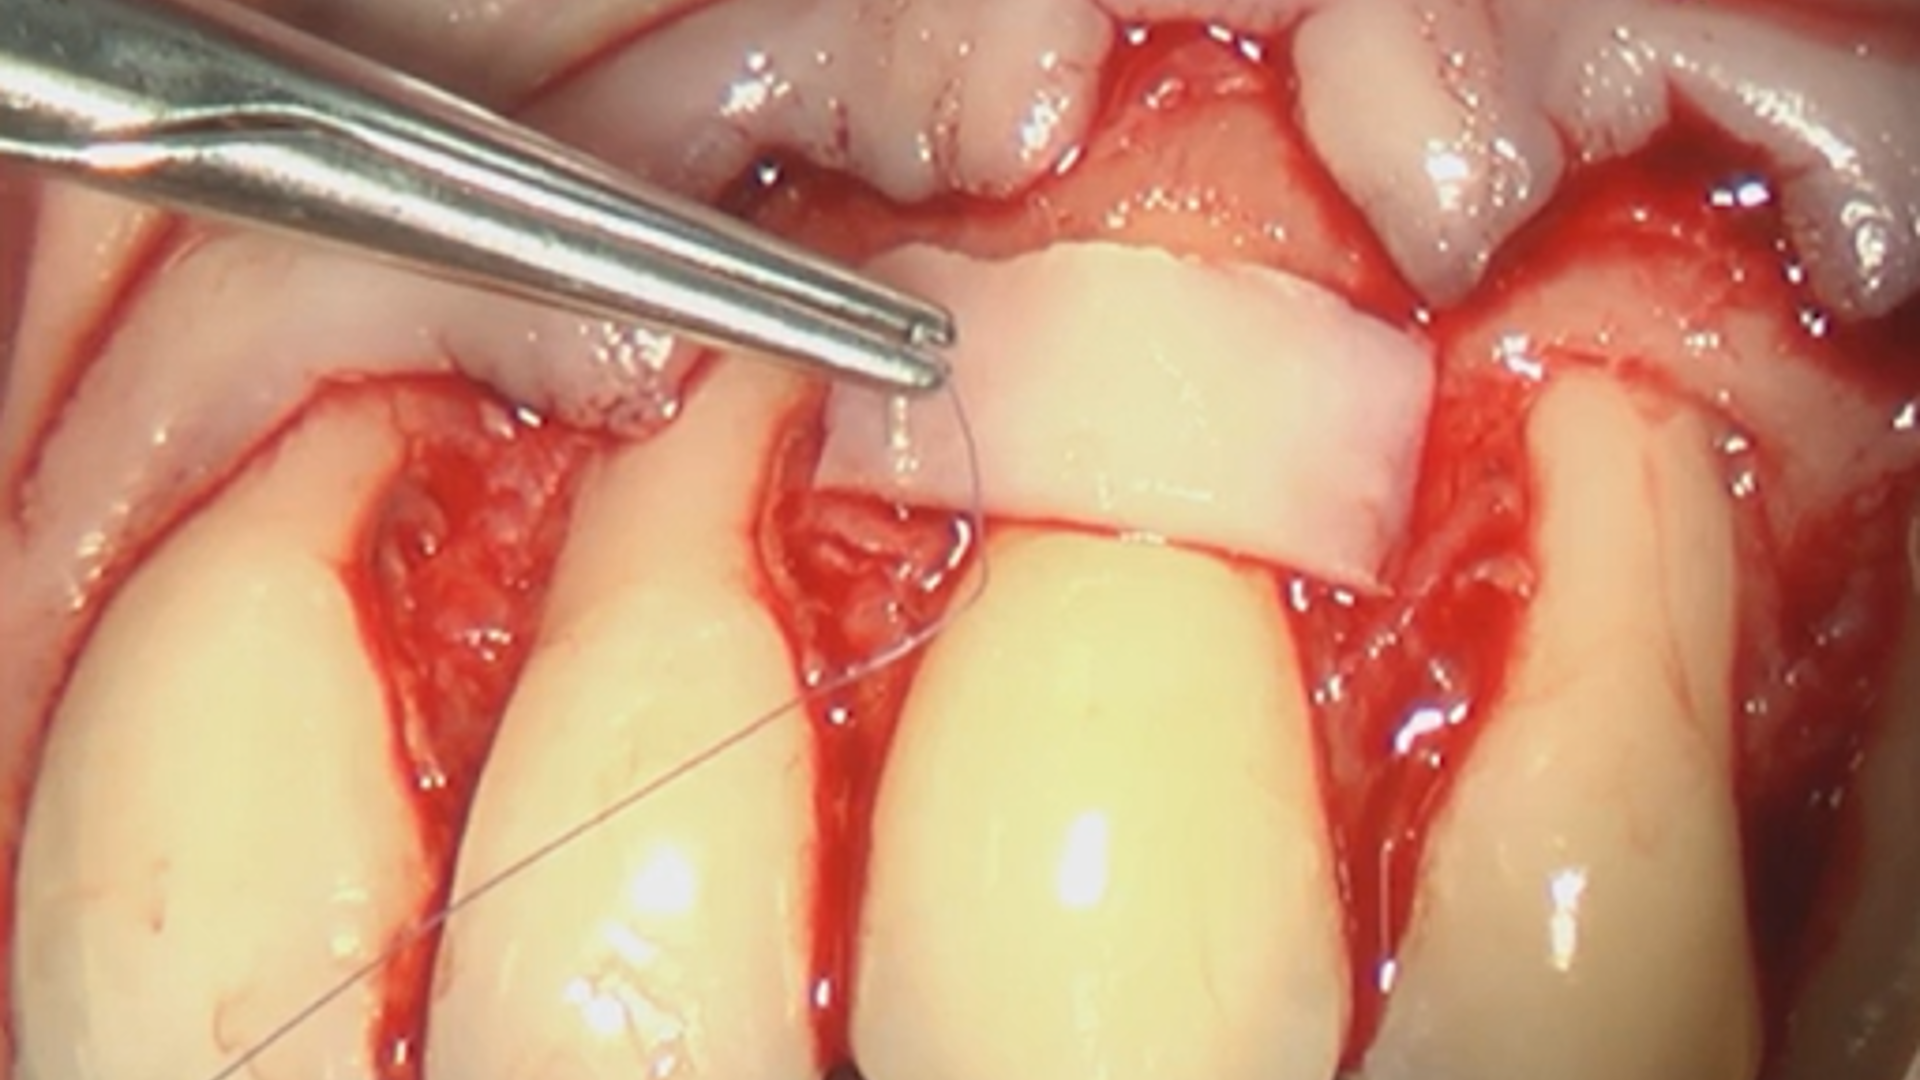

Entire surgical procedure: Coronally Advanced Flap and Connective Tissue Graft

Hands-On Video Part 4 - Suture protocol